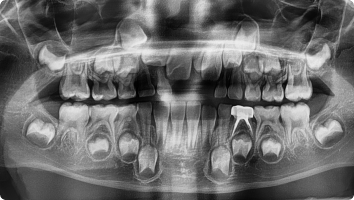

함치성 낭종은 나지 않은 치아(주로 사랑니, 송곳니) 주위에 생기는 물주머니(낭종)입니다.

치아가 잇몸 속에서 올라오지 못하고 머물면서 그 주위에 액체가 고여 발생합니다.

- 흔히 사랑니나 매복된 송곳니에서 발견됩니다.

- 크기가 커지면 주변 뼈를 흡수하거나, 옆 치아 뿌리를 밀어 손상시킬 수 있습니다.

- 대부분 통증이 없어 정기적인 X-ray 검사에서 우연히 발견되는 경우가 많습니다.

- 국소마취 후 잇몸을 열어 낭종과 함께 원인 치아를 제거합니다.

- 낭종 벽을 깨끗이 적출하여 재발을 막습니다.

- 병리검사를 통해 정확한 진단을 확인합니다.

- 작은 경우는 간단히 제거가 가능하고, 큰 경우는 단계적으로 치료하기도 합니다.